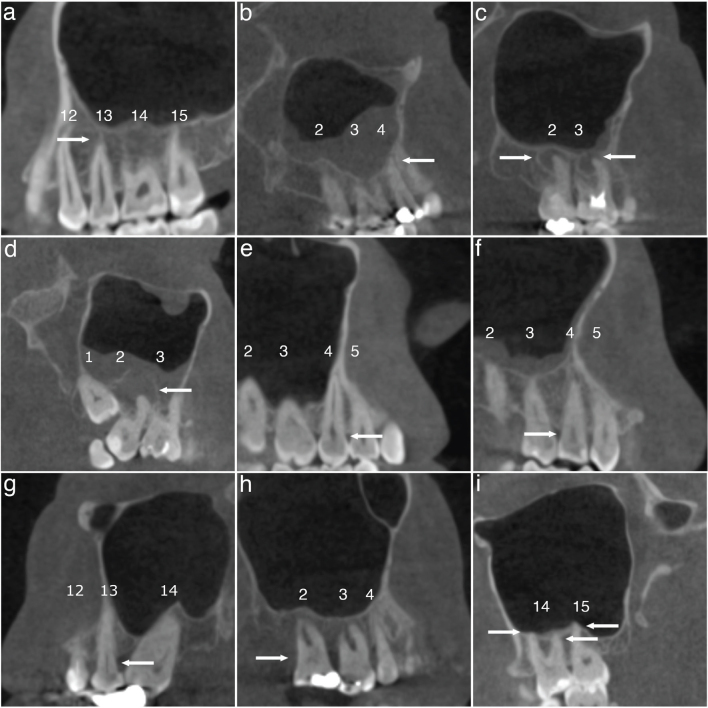

Objective: To evaluate maxillary sinus and odontogenic findings in low-dose CBCT, and to test if associations exist between these findings.  Methods: From 263 consecutive CBCT scans, 212 were included. Evaluated odontogenic parameters were periapical lesions (PAI), marginal periodontal bone loss (PBL), root contact to the maxillary sinus, the presence of crowns, implants, defective restorations and extensive caries. Maxillary sinus findings were categorized as mucosal thickening (MT; generalized and localized), mucosal retention cysts, and opacification/fluid level. Crosstabulations and generalized estimating equations were used as statistical tests. Prevalence and bias adjusted kappas were calculated for inter- and intra-observer agreement.

Results: The only dental finding statistically associated with sinus pathology when compared to healthy sinuses was root contact, which increased the risk for generalized MT (OR = 1.47, p = 0.015), mucosal retention cysts (OR = 2.60, p < 0.001) and opacification/fluid (OR = 1.76, p = 0.018). All parameters showed almost perfect or substantial intra- and interobserver reliability, except for PBL, where the former was moderate and the latter fair.

Conclusion: Root contact was the only dental finding significantly associated with sinus pathology. Thus, there may be fewer associations between radiological dental findings and sinus pathology than previously thought. With the exception of PBL, all parameters demonstrated at least substantial intra- and interobserver reliability, indicating that the assessment is reliable overall.